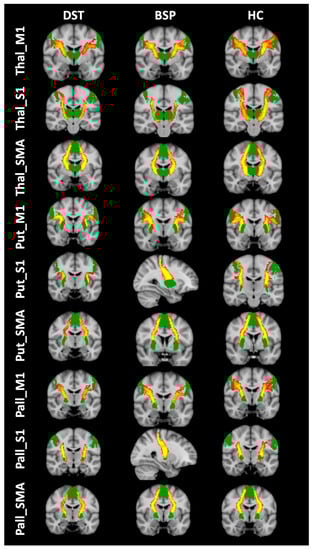

2.3.2. Tractography